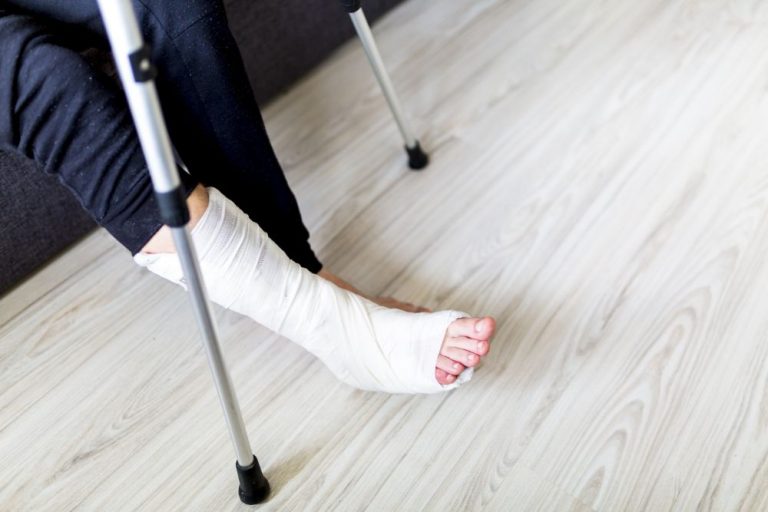

Broken bone cases are considered serious injuries because of the potential long-term effects they can have on an individualโ€™s future ability to work and quality of life. Fractures can be the result of a workplace accident, especially on construction sites, however, that is not to... (Keep Reading)

How To File A Broken Bone Injury Claim In New York City